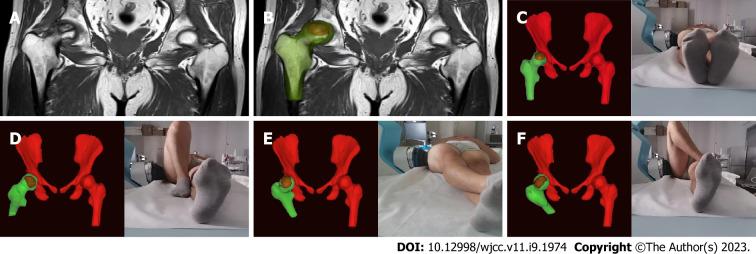

This was a randomized, controlled, double-blinded, non-inferiority trial. We examined 80 patients for eligibility in this study; 8 patients were excluded based on inclusion and exclusion criteria. A total of 72 subjects with ONFH were randomly assigned to group A ( = 36; celecoxib + alendronate + sham-placebo shock wave) or group B ( = 36; individual focused shock wave [ESWT based on magnetic resonance imaging three-dimensional (MRI-3D) reconstruction] + alendronate). The outcomes were assessed at baseline, at the end of treatment, and at an 8-wk follow-up. The primary outcome measure was treatment efficiency after 2 wk of intervention using the Harris hip score (HHS) (improvement of 10 points or more from the baseline was deemed sufficient). Secondary outcome measures were post-treatment HHS, visual analog scale (VAS), and Western Ontario and McMaster Universities Osteoarthritis Index (WOMAC) scores.

这是一项随机、对照、双盲、非劣效性试验。我们检查了80例患者是否符合本研究的入选标准;根据纳入和排除标准排除了8例患者。总共72例ONFH患者被随机分为A组(n = 36;塞来昔布+阿仑膦酸钠+假安慰剂冲击波)或B组(n = 36;个体化聚焦冲击波[基于磁共振成像三维(MRI-3D)重建的ESWT]+阿仑膦酸钠)。在基线、治疗结束时和8周随访时评估结果。主要结局指标是使用Harris髋关节评分(HHS)在干预2周后的治疗效率(与基线相比提高10分或更多被认为是足够的)。次要结局指标是治疗后的HHS、视觉模拟量表(VAS)和西安大略和麦克马斯特大学骨关节炎指数(WOMAC)评分。